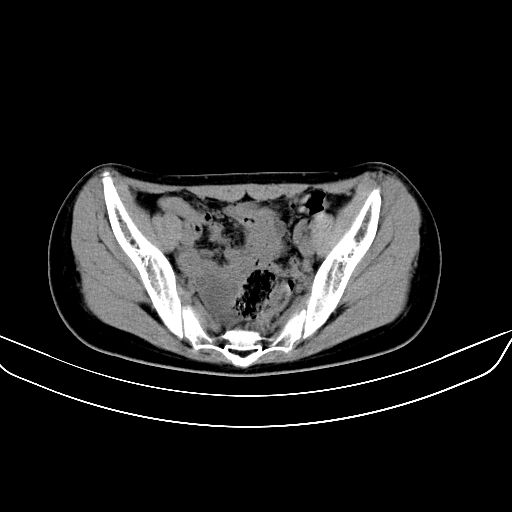

以下是引用zsl6918在2008-7-11 21:40:00的发言:[br]双侧骶髂关节骨质破坏以下三分之一为主,符合强直性脊柱炎表现

以下是引用zhangzhongshou在2008-7-11 21:41:00的发言:[br]患者是女性,hla-b27抗原(—),首先不太考虑强直性脊柱炎,建议查类风湿因子,骶髂关节改变考虑类风湿性关节炎可能性大,建议进一步检查。